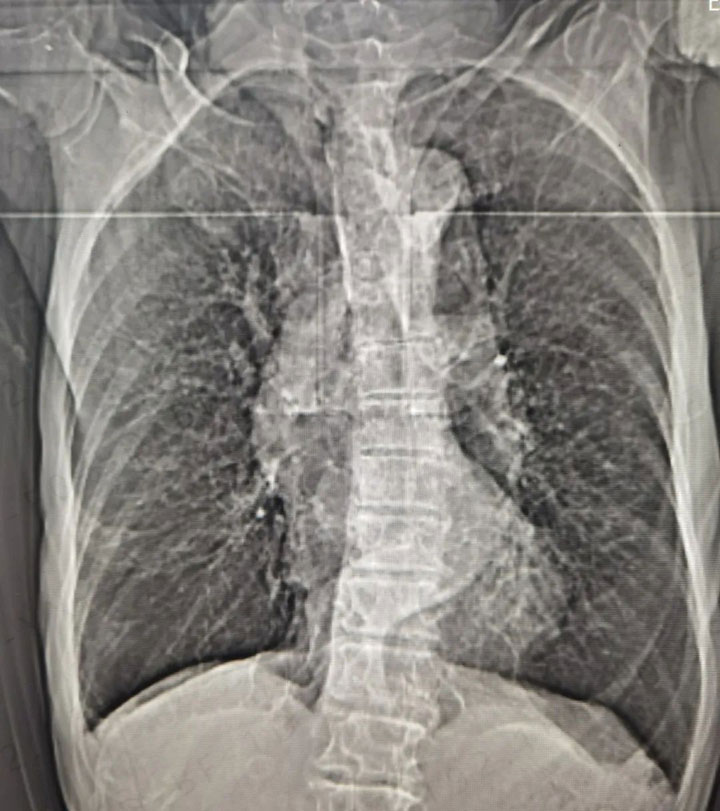

呼吸内科副主任史和平表示,慢性阻塞性肺疾病严重危害我国人民群众身体健康,患病率较高,我国40岁及以上居民慢性阻塞性肺疾病患病率高达13.6%,患者人数近1亿。但其患病知晓率为0.9%,肺功能检查率为4.5%,呈现出患病率高、知晓率低、规范化诊疗率低的特点,慢性阻塞性肺疾病科普教育、早期预防、早期诊断和规范治疗亟待加强。

呼吸内科温馨提示,当慢性阻塞性肺疾病患者出现气促、喘息、胸闷、咳嗽加重,发热,痰量增加、颜色和(或)粘稠度改变等,提示可能发生了慢性阻塞性肺疾病急性加重,需尽快前往专业的医院就诊。